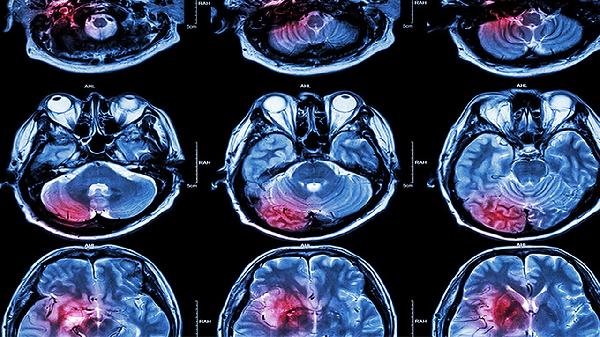

ADHD等神经发育问题会导致思维不受控地跳跃。专注力测试结合脑电图检查可确诊,药物治疗包括哌甲酯缓释片、托莫西汀等,行为疗法中番茄工作法配合白噪音训练效果显著。

饮食方面增加富含磷脂酰丝氨酸的三文鱼、核桃等食物有助于提升专注力,每天20分钟有氧运动如跳绳可促进脑源性神经营养因子分泌。建立考试专用行为仪式如固定颜色的文具能形成条件反射式的专注状态,长期存在症状需通过连续性执行功能测试排除神经系统病变。